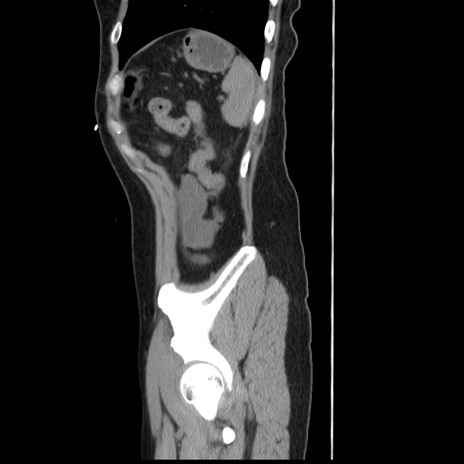

横断像

冠状断像

【症例】 50歳代女性

【主訴】 腹痛

【現病歴】前日生レバーを食べた。今朝に排便あり。 昼前に突然発症の腹痛を生じ、当院救急外来を受診した。

【既往歴】 子宮筋腫にてで子宮全摘後

【身体所見】 意識清明、腹部:平坦、軟、下腹部やや左を中心に圧痛・反跳痛あり、筋性防御あり

【データ】WBC 7800、CRP 0.07